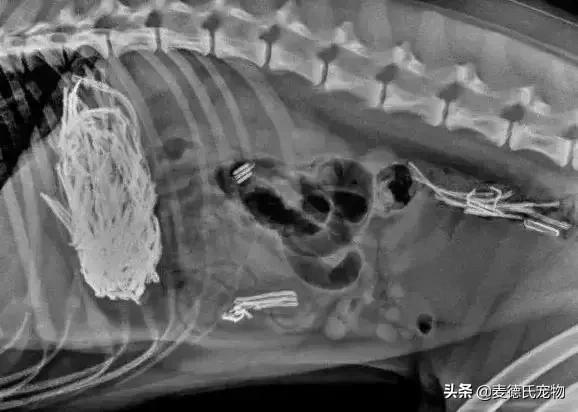

不少宠物医院也经常会放一些X光片来提醒铲屎官注意狗狗吞食异物的现象:

据说,下面这货吞食了女主人一整个胸罩...

这只狗砸吞了主人的假牙,因为装假牙的碗里有冰淇淋残渣...

此外,还有勺子...

刀子...

玩具汽车?

绳结线团...

鱼钩...

不明三角...